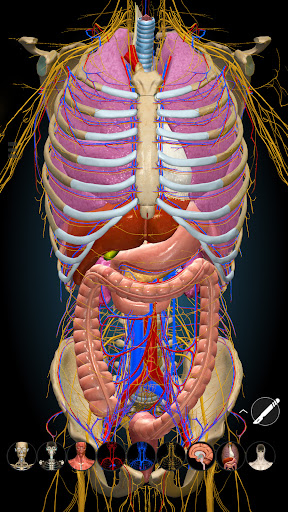

★ Remove structures to reveal the anatomical structures below them.

★ Switch on/off different anatomy systems

★ Circulation (arteries, vein and heart)

★ Central nervous system

★ Peripheral nervous system

★ Respiratory

★ Digestive

★ Urinary